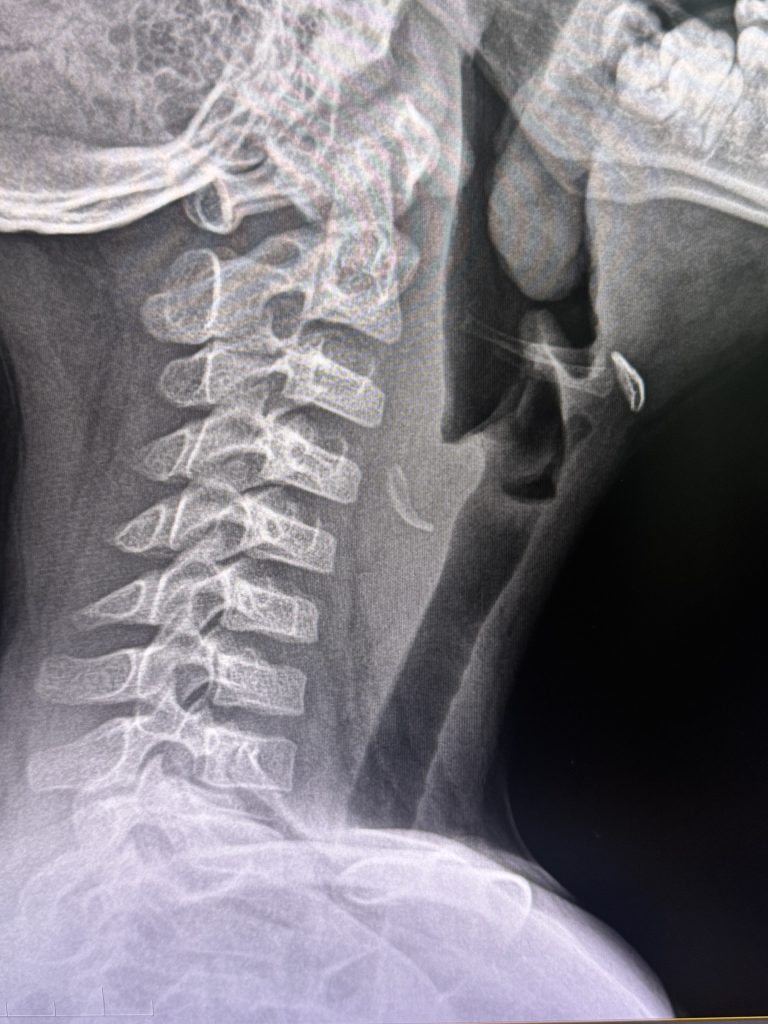

Hình ảnh chụp Xquang thực quản cổ nghiêng cho thấy: tăng đậm độ cản quang vị trí phần mềm trước cột sống cổ ngang mức đốt sống C4, kích thước ~5×24 mm.